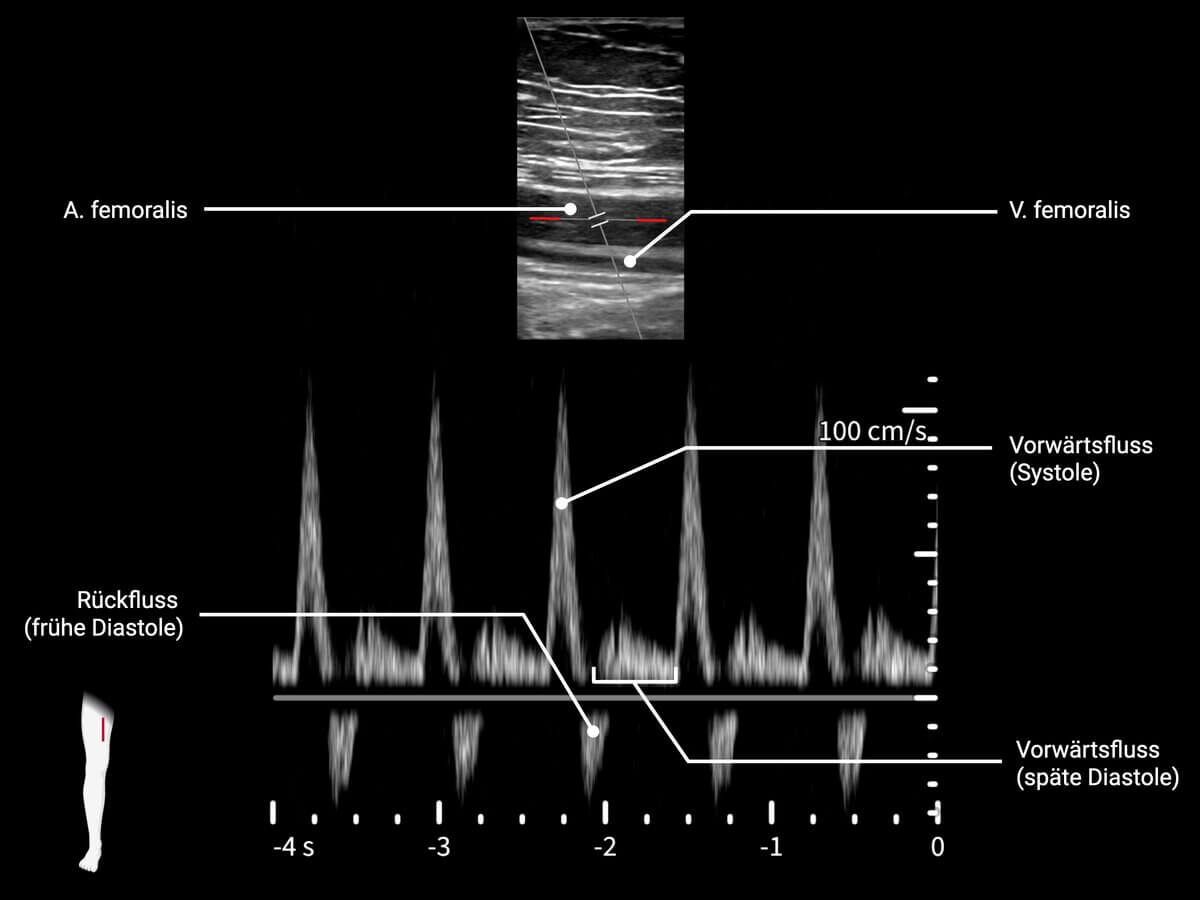

Als Flussprofil bezeichnet man in der Dopplersonographie die zeitliche und räumliche Verteilung der Blutflussgeschwindigkeit innerhalb eines Gefäßes. Es wird aus der frequenzabhängigen Verschiebung des reflektierten Ultraschallsignals abgeleitet. Das Flussprofil erlaubt Rückschlüsse auf hämodynamische Verhältnisse, Gefäßwiderstände und pathologische Veränderungen des Gefäßlumens.

- triphasisches Flussprofil: entsteht durch Vorwärtsfluss in der Systole (1. Phase), kurzen Rückfluss in der frühen Diastole (2. Phase) und erneuten Vorwärtsfluss in der späten Diastole (3. Phase). Ursache ist ein hoher peripherer Widerstand, typisch für gesunde periphere Arterien